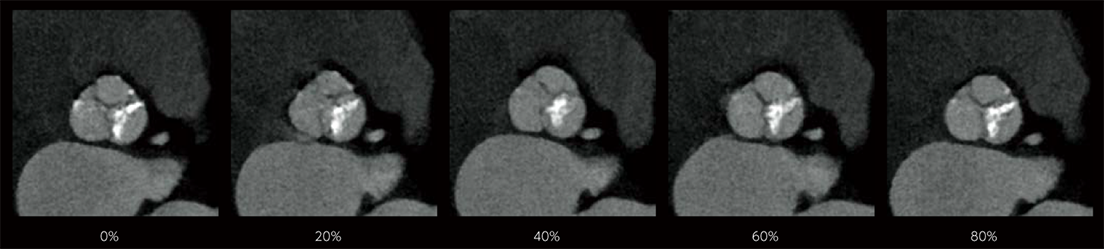

In cardiac CT examinations, the various factors such as heart rate and heart movement affect image quality. With conventional image reconstruction methods, unfocused coronary arteries and artifacts caused by motion could occur, resulting in images not meeting the expected quality, which could affect the diagnosis. To help resolve these problems, Fujifilm developed Cardio StillShot, which calculates the direction and amount of movement of the subject in four dimensions based on the raw data collected during cardiac CT examinations, and corrects it during image reconstruction to achieve an effective time resolution of 28 msec.*1 The effective time resolution contributes to improved diagnostic capability by providing high-definition focused clinical images with less motion artifacts even in patients with a high heart rate.

- *1 With 0.35 sec/rot and beam pitch of 0.1719

Cardio StillShot: OFF

Cardio StillShot: ON